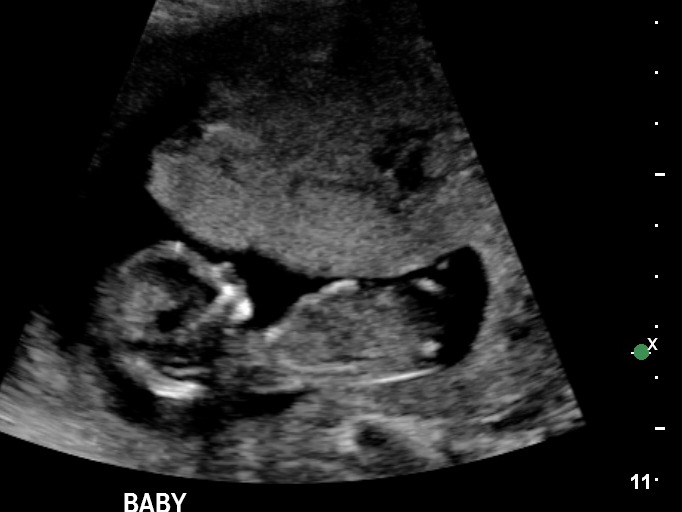

If the nub is that bottom bit then girl but it sure is hard to tell what's going on down there.

I'm leaning boy, but am not really good at this. Good luck and congrats on a sweet baby!

I really don't think there is a nub there. The bottom half has been cut off. Gorgeous baby though! Hope you get your DG :)

was wondering if anyone would guess based on skull? i didnt think that was a nub lol although someone asked, if that was a willy....i said i DONT think so!!

Going for boy based on the flat forehead just a guess I can't see nub either